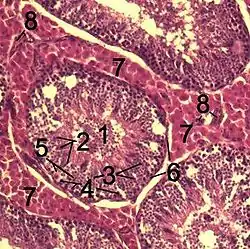

![]() Гістологічний зріз через тестикулярну перенхіму кабана. 1 сімяні канальці Tubulus seminiferus contortus 2 сперматиди 3 сперматоцити 4 Сперматогонії 5 клітини Сертолі 6 Міофібробласти 7 клітини Лейдігаs 8 капіляри | |